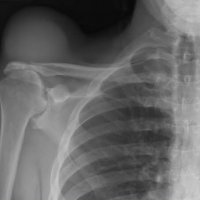

THE GEYSER SIGN IS A SUBCUTANEOUS PSEUDOTUMOR ABOVE THE ACROMIOCLAVICULAR JOINT

The geyser sign is a subcutaneous pseudotumor above the acromioclavicular joint, also known as AC joint cyst. The geyser sign is an infrequently encountered imaging sign that was originally described on conventional fluoroscopy-guided shoulder arthrography. The first case report of these cysts occuring in association with rotator cuff tears was made by Dr. Edward Craig in 1984, and again in 1986. The sign derives its name from its geyser-like appearance.

On physical examination, an AC joint cyst is a palpable fluid-filled mass. MRI scanning or a shoulder arthrogram should be obtained to evaluate the shoulder. Unenhanced MRI scans showing a large rotator cuff tear, a degenerated AC joint, and a large subcutaneous cyst adjacent to the AC joint is virtually patognomonic for the disease. Contrast administration on MR arthrogram will show the synovial fluid or intra-articular contrast extravasates from the glenohumeral joint into the subacromial bursa, into the AC joint, and then into an overlying cystic mass when a full-thickness rotator cuff tear is present, resembling a geyser spouting upwards.

Initial treatment is conservative and involves physical therapy along with aspiration. In patients with functional impairment or chronic shoulder pain who have failed conservative management, surgical treatment is recommended for both excision of the cyst and repair of the rotator cuff tear.